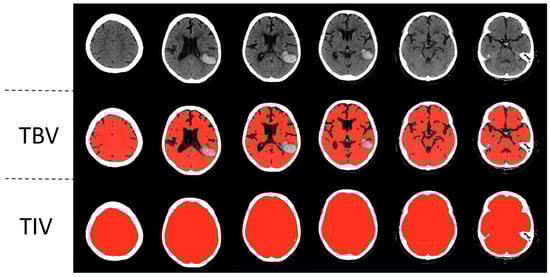

To measure the total brain volume and the total intracranial volume, a previously published automated head CT segmentation method (CTseg: https://github.com/NuroAI/CTSeg, accessed on 1 September 2020), was used (see Figure 1). This method has been previously published elsewhere [16]. Briefly, it employs the adapted unified segmentation algorithm from SPM Toolbox, Version 12, and incorporates a CT template to initiate the affine registration process.

Figure 1. Automatic segmentation of a left parietotemporal lobar intracerebral hemorrhage. Segmentations of total brain volume (TBV) and total intracranial volume (TIV) are in the second and third rows, respectively.

SPM 12 itself is a broadly applied algorithm that is used mostly for the MRI segmentation of different parts of the brain, e.g., gray matter, white matter, or cerebral spinal fluid. First, the likelihood of each voxel belonging to a specific structure is calculated. This generates a probabilistic map. It gradually modulates the intensity distribution of the various brain tissues and then calculates the probability for each tissue using the Bayes rule. Next, spatial normalization is performed by adapting the standard tissue probability map to the calculated probabilistic map. This method is independent of the absolute tissue intensity of the original image. Thus, this method is applicable to different modalities. Here, CTSeg applies this algorithm to CT images. For this purpose, a CT template was used, which was compared with a standardized MR imaging template. As a first step, the voxel intensities of the CT image are adjusted to match the intensity space of the CT template. Secondly, The CT image is aligned with the CT template to secure the correct spatial orientation. Then, the registered CT image is segmented using SPM to create tissue probability maps for the different tissues. These maps represent the probability that a certain region of the image belongs to a specific type of tissue. Afterward, the probability maps are transformed back to the original space of the CT image. Finally, the probability maps are converted into binary maps by applying optimal threshold values. If a specific pixel surpasses this specific threshold, it is finally labeled as a specific tissue. This is how the final segmentation map is generated [16,17].

This method has shown excellent agreement with manually segmented head CTs for both intracranial volume and total brain volume in the past [16]. CTseg has already been successfully applied in different studies. For example, it was used to describe how brain atrophy increases in septic ICU patients [18]. In another study, it was applied to show how brain atrophy affects the effect of endovascular therapy in patients with acute ischemic stroke due to large vessel occlusion [19]. To validate this method, we performed an additional analysis on 23 randomly selected consecutive head CT scans, which were independently assessed by an experienced neuroradiologist using the GCA visual atrophy score adapted for total brain volume. The results showed excellent agreement with the automated brain volume measurements (rs = −0.87369, p < 0.001) using Spearman’s rank correlation test.